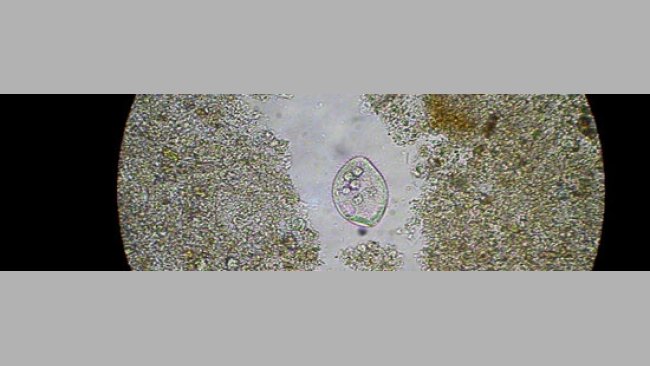

Caso clínico: Diarreas en lechones lactantes debidas a Clostridium perfringens

Se observó una diarrea sanguinolenta en lechones de 2-3 días de vida, que cursaba con una elevada mortalidad.